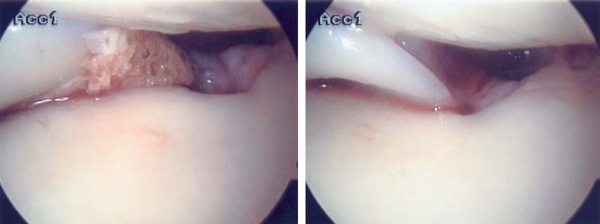

After combined ACL and meniscal transplantation surgery, good results are achieved in nearly 85% of patients (

Fig. 50-13

). The senior author’s results are presented in

Table 50-1

. Other authors’ results of meniscus transplantation are presented elsewhere in this book and referenced.

Figure 50-13 |